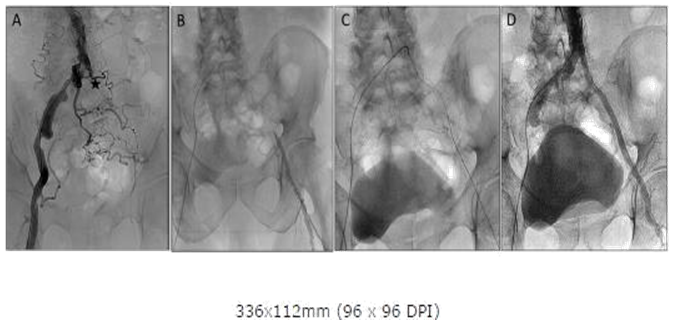

Right Common Femoral Artery (CFA) access was obtained and abdominal angiogram revealed a left proximal Iliac occlusion (Figure 1A) with reconstitution at the left femoral bifurcation (Figure 1B). Left CFA access was obtained with fluoroscopic guidance and a 6 Fr sheath placed in the Left CFA. Attempts were made with a 0.035 angled glidewire through the 6 Fr sheath from below but were unsuccessful in crossing the distal cap of the occlusion and a the wire was noted to enter a subintimal plane. A CC was advanced from the Right CFA and pulled down to firmly clip the aortic bifurcation (Figure 1C). A 0.035 stiff angled glidewire was then slowly advanced through the PICTO from the CC above without catheter back out and able to exit into the true lumen below. The wire was then snared and externalized through the Left CFA sheath. Once the wires were positioned true lumen to true lumen, the rest of the case was finished using standard stenting techniques and the left PICTO was recanalized with an excellent angiographic result (Figure 1D). The patient was claudication free at 1 month follow up without any complications.

Figure 1A: Abdominal Aortogram showing Left Common Iliac occlusion and proximal cap (asterisk). Note previous stent in Left common iliac.

Figure 1B: Angiography from sheath inserted in Left femoral showing dissection due to attempts at retrograde crossing from left.

Figure 1C: Contra catheter with angled glide from right seated at bifurcation with clip like action providing support for crossing occlusion.

Figure 1D: Abdominal Aortogram post stenting showing good angiographic result.